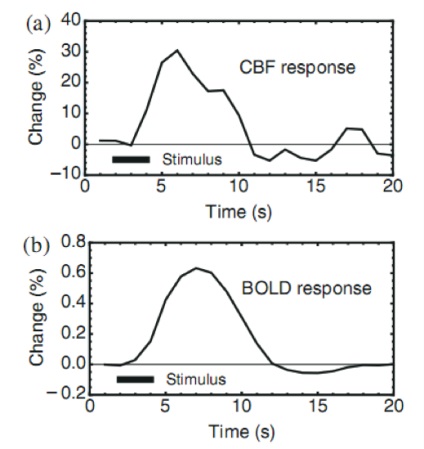

BOLD fMRI - aceasta este una dintre metodele cele mai utile și larg cunoscute pentru a determina activitatea creierului. Activarea conduce la creșterea fluxului sanguin local, cu o modificare a concentrației relative a hemoglobinei oxigenate (sărac în oxigen) (oxigen-bogat) și dezoxigenata fluxului sanguin local.

sânge dezoxigenat este paramagnetic (substanță capabilă de a fi magnetizat) și conducând la nivelul de semnal RMN picătură. Dacă în zona a creierului mai mult sange oxigenat - semnal IRM crește nivelul. Astfel, oxigenul din sânge acționează ca un agent de contrast endogen.